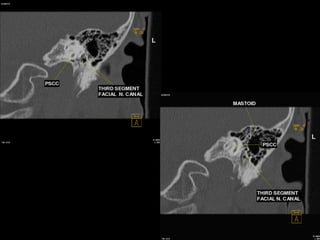

 Posterior semicircular canal (PSCC)

orientated in the vertical plane parallel to the long axis of the PTB

hair cells of the posterior semicircular duct supplied by the inferior division of CN

VIII

Segments

 tympanic segment (from geniculate ganglion to pyramidal eminence): 8-11 mm

long, zero branches

 mastoid segment (from pyramidal eminence to stylomastoid foramen): 8-14 mm long, 3

branches